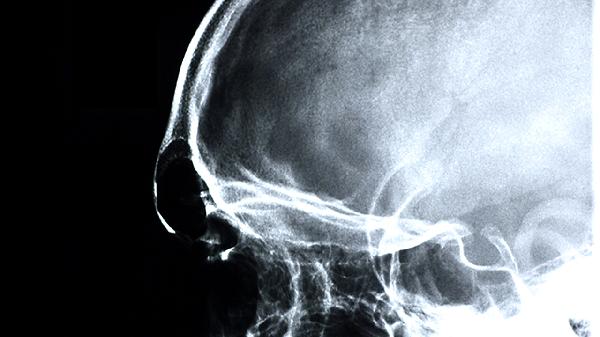

长期脑动脉硬化造成脑组织慢性缺血的患者,若出现反应迟钝、记忆力下降等认知功能障碍,可在医生评估后使用该药。药物通过扩张脑血管改善供氧,延缓认知功能恶化。需注意该药不能替代降压、降脂等基础治疗,应联合控制血压血脂。服药期间出现头晕加重需及时就诊,避免与抗凝药物同时使用。